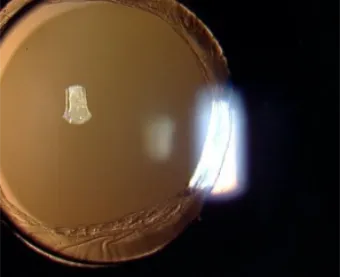

Post PPL- AB - Externo 4 Point Sutured Scleral Fixation

Visual Rehabilitation of a patient born with Congenital cataract and had undergone Pars Plana Lensectomy 25 years back. The patient was visually rehabilitated by a modified Sutured Scleral Fixation Surgery